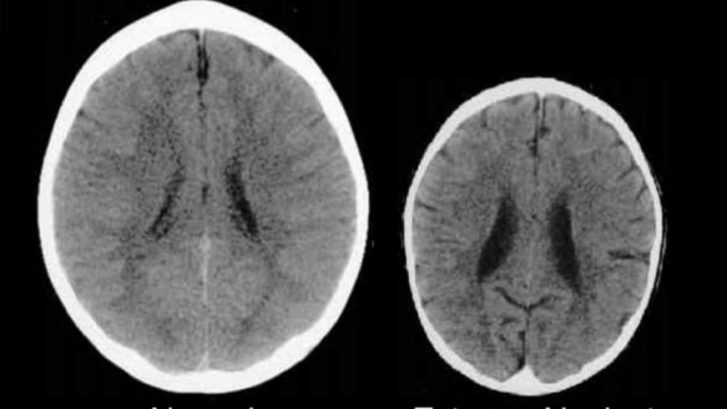

Aunque viendo esta imagen muchos pensaréis que se trata de dos niños de diferentes edades, la realidad (por desgracia) es que son de dos niños de tres años de edad con un cerebro muy diferente, no porque haya diferencias en el nacimiento, enfermedad o similar, sino porque mientras a uno lo han cuidado y querido, al otro no.

En resumidas cuentas, y ahora hablamos de ello, la imagen de la derecha muestra lo que le pasa al cerebro de un bebé, luego niño, cuando nadie lo atiende según sus necesidades.

Esta imagen tan sorprendente, y que tanto nos duele porque imaginamos la vida que ha podido tener ese pequeño, proviene de un artículo del profesor Bruce D. Perry, jefe de psiquiatría del Texas Children’s Hospital, a la que se refiere con estas palabras:

La tomografía computarizada de la izquierda es una imagen de un niño sano de 3 años, con un tamaño de cabeza promedio. La imagen de la derecha es de un niño de 3 años que sufre de negligencia severa de cuidados y privación sensorial. El cerebro de este niño es significativamente más pequeño que el promedio y tiene los ventrículos agrandados y atrofia cortical.

El niño de la derecha de la imagen es uno de ellos, como tantos otros cientos de niños que han sido estudiados en un momento u otro y que han demostrado lo que todos imaginamos, que crecen con menos sustancia blanca que los niños normales, con afectación importante en las áreas de la atención, el procesamiento sensorial, la función ejecutiva y las regiones responsables de las emociones.